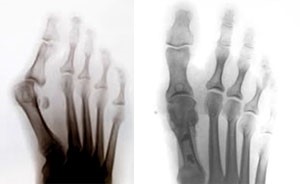

• операции при Hallux Valgus ("косточки на ногах"), поперечном плоскостопии, болезненных натоптышах - коррегирующие остеотомии SCARF, Chevron, Akin, Weil https://www.youtube.com/watch?v=7BF-Y5XJr6Y